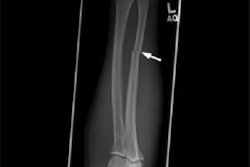

- Spiral fracture